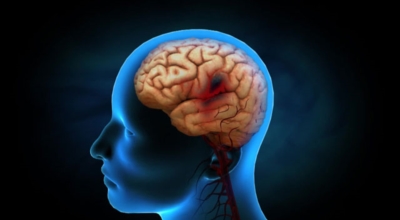

뇌졸중 후유증

뇌졸중이 치명적인 이유는 한 번 훼손된 뇌 조직은 다시 좋아지지 않기 때문입니다. 뇌졸중은 발생 후 시간이 지날수록 점점 진행되므로 빠른 치료가 생명인데요 시간이 지나면서 훼손된 부분의 기능을 다른 정상적인 조직이 도움 줌으로 인해 증상이 개선될 수는 있으나 치료 시기가 늦을수록 치료 효과는 감소시키며 역효과가 더 커지며 후유증이 크게 남을 수 있어요.

초기 뇌경색이 진행하거나 재발할 수 있으므로 뇌졸중 진행을 막기 위하여 빨리 내원해서 치료해야 한다는 점이 중요해요. 급성 뇌졸중 치료가 종료된 이후 뇌졸중 환자들은 여러 부분 일정 양의 장애를 갖게 되는데 적극적이고 빠른 재활치료를 통해 육체 기능이 호전되는 것이 가능해요.

뇌세포는 몇 분만 혈액공급이 안 되어도 훼손을 입게되고 한 번 죽은 뇌 세포는 다시 살릴 수 없게 되어 빠른 치료가 주요한 질병입니다. 뇌세포가 훼손되는 시간은 발병 후에 3시간에서 최대 6시간이면 손을 쓸 수 없이 훼손을 받기 때문에 뇌졸중을 담당하는 의사들은 뇌졸중의 골든타임을 발병 3시간에서 6시간 이내로 보고 있다고 합니다. 그러므로 발견 즉시 병원으로 가서 치료를 받으시는 것이 중요하다는 점 기억하세요.